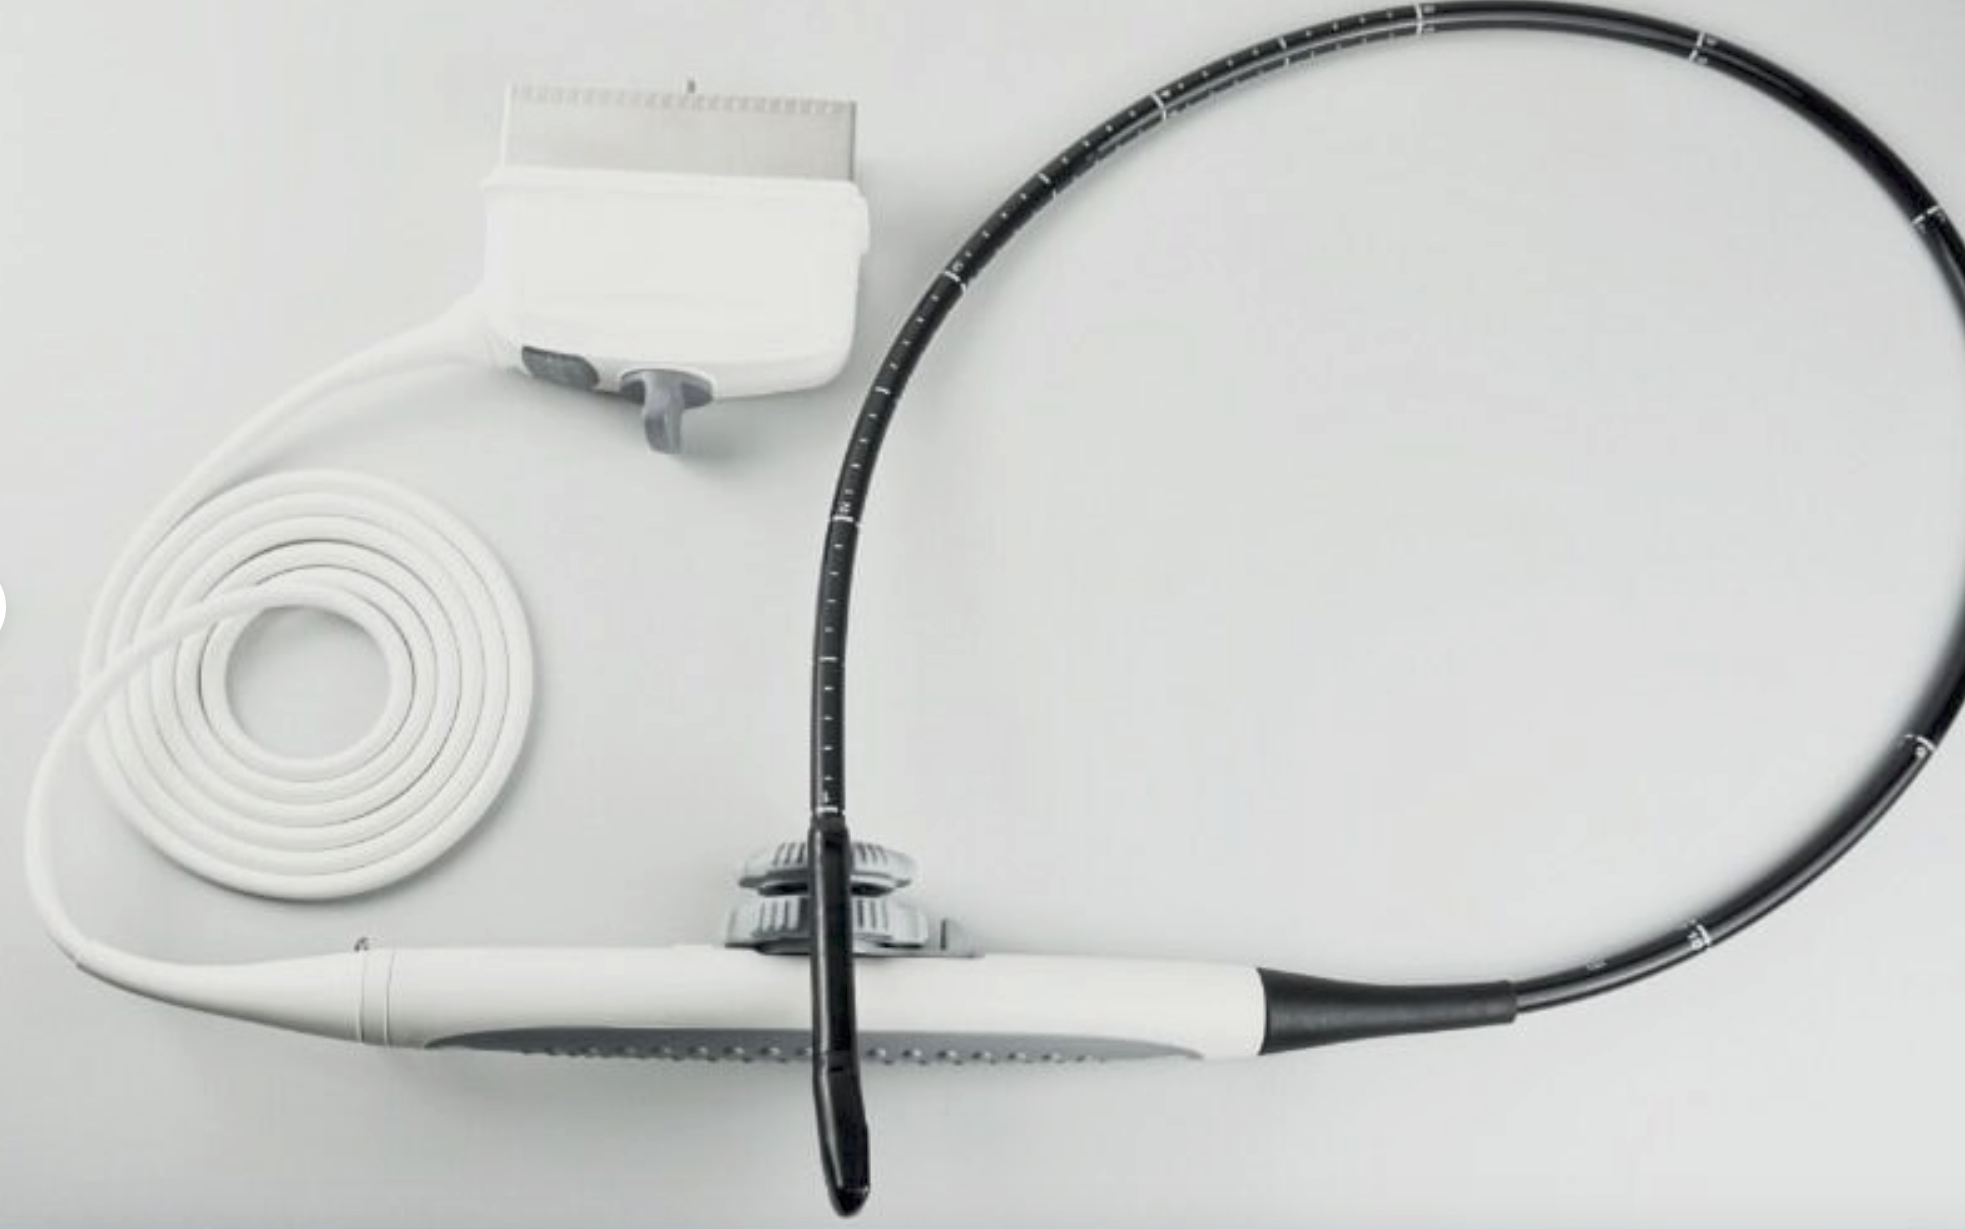

The SONOSITE TITAN OB/GYN ultrasound offers state-of-the-art imaging technology. This device uses advanced algorithms to provide clear, high-resolution images. It includes two probes: a 1-C60 convex and a 1-ICT transvaginal probe, ensuring versatility in different obstetric and gynecological applications. Because of its compact design, the SONOSITE TITAN is perfect for both hospital and remote settings, making it an ideal choice for healthcare providers.